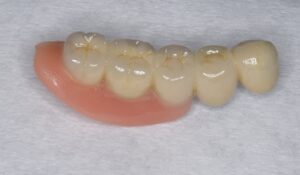

ケース2:上下に多くの問題があった70代後半男性

この方は虫歯や歯周病で残存歯が少なく、グラグラの歯が多い状態でした。最初は保険のクラスプ義歯を入れていたものの安定せず、硬いものを噛めないため外していることが多かったそうです。外見を重視してナイロン義歯を試されましたが、期待したような咬合回復は得られず、全体の再治療を希望して来院されました。

まず全顎の虫歯と歯周病の治療を行い、上顎は残存歯すべてに内冠をかぶせて連結し、全体を支えるテレスコープ義歯を製作しました。装着後は「入れ歯」というよりは取り外し可能な長いブリッジの感覚で、違和感がほとんどないとのことです。

このケースは「残った歯をチーム化して守る」発想が有効であった例です。